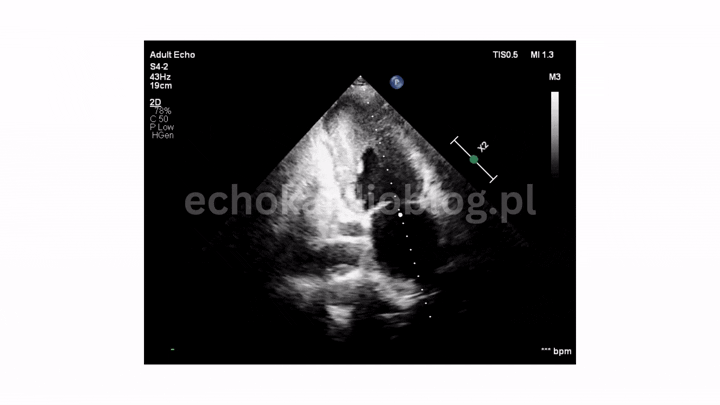

Pacjent , lat 66, przyjęty z podejrzeniem sepsy, w badaniu echokardiograficznym ujawniono duże, ruchome wegetacje na trzech zastawkach – mitralnej, trójdzielnej i płucnej . Wegetacje najlepiej widoczne były w projekcjach podmostkowych . Obraz jest dramatyczny: wysokie ryzyko powikłań zatorowych i przeciążenia prawego serca.

A 66-year-old patient admitted with suspected sepsis underwent echocardiography, revealing large, mobile vegetations on the mitral ,tricuspid and pulmonary valves .Vegetations were most clearly visualized in subcostal projections. The findings are dramatic, indicating a high risk of embolic complications and right heart overload.

ciężka niedomykalność płucna w projekcji podmostkowej

dwie długie i bardzo ruchome wegetacje na płatkach zastawki płucnej – pr podmostkowa w osi krótkiej